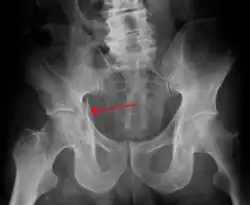

Acetabular fracture

| Acetabular fracture as seen on plain X-ray |

Fractures of the acetabulum occur when the head of the femur is driven into the pelvis. This injury is caused by a blow to either the side or front of the knee and often occurs as a dashboard injury accompanied by a fracture of the femur.[1]